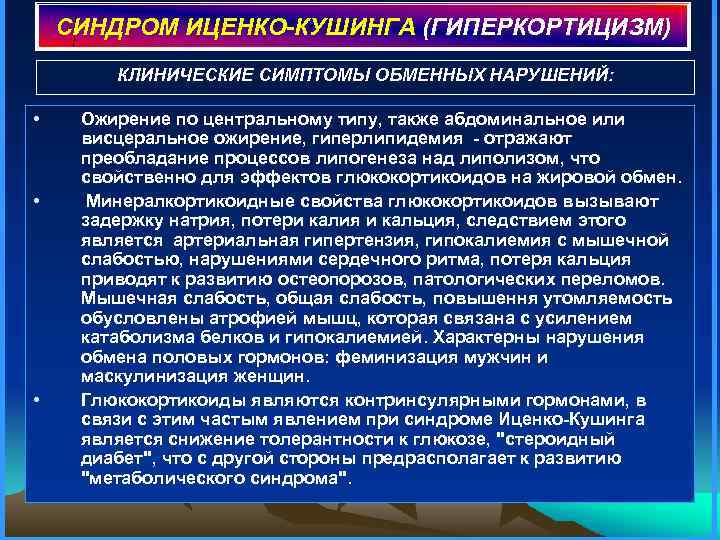

СИНДРОМ ИЦЕНКО-КУШИНГА (ГИПЕРКОРТИЦИЗМ) КЛИНИЧЕСКИЕ СИМПТОМЫ ОБМЕННЫХ НАРУШЕНИЙ: • • • Ожирение по центральному типу, также абдоминальное или висцеральное ожирение, гиперлипидемия - отражают преобладание процессов липогенеза над липолизом, что свойственно для эффектов глюкокортикоидов на жировой обмен. Минералкортикоидные свойства глюкокортикоидов вызывают задержку натрия, потери калия и кальция, следствием этого является артериальная гипертензия, гипокалиемия с мышечной слабостью, нарушениями сердечного ритма, потеря кальция приводят к развитию остеопорозов, патологических переломов. Мышечная слабость, общая слабость, повышення утомляемость обусловлены атрофией мышц, которая связана с усилением катаболизма белков и гипокалиемией. Характерны нарушения обмена половых гормонов: феминизация мужчин и маскулинизация женщин. Глюкокортикоиды являются контринсулярными гормонами, в связи с этим частым явлением при синдроме Иценко-Кушинга является снижение толерантности к глюкозе, "стероидный диабет", что с другой стороны предрасполагает к развитию "метаболического синдрома".

СИНДРОМ ИЦЕНКО-КУШИНГА (ГИПЕРКОРТИЦИЗМ) КЛИНИЧЕСКИЕ СИМПТОМЫ ОБМЕННЫХ НАРУШЕНИЙ: • • • Ожирение по центральному типу, также абдоминальное или висцеральное ожирение, гиперлипидемия - отражают преобладание процессов липогенеза над липолизом, что свойственно для эффектов глюкокортикоидов на жировой обмен. Минералкортикоидные свойства глюкокортикоидов вызывают задержку натрия, потери калия и кальция, следствием этого является артериальная гипертензия, гипокалиемия с мышечной слабостью, нарушениями сердечного ритма, потеря кальция приводят к развитию остеопорозов, патологических переломов. Мышечная слабость, общая слабость, повышення утомляемость обусловлены атрофией мышц, которая связана с усилением катаболизма белков и гипокалиемией. Характерны нарушения обмена половых гормонов: феминизация мужчин и маскулинизация женщин. Глюкокортикоиды являются контринсулярными гормонами, в связи с этим частым явлением при синдроме Иценко-Кушинга является снижение толерантности к глюкозе, "стероидный диабет", что с другой стороны предрасполагает к развитию "метаболического синдрома".